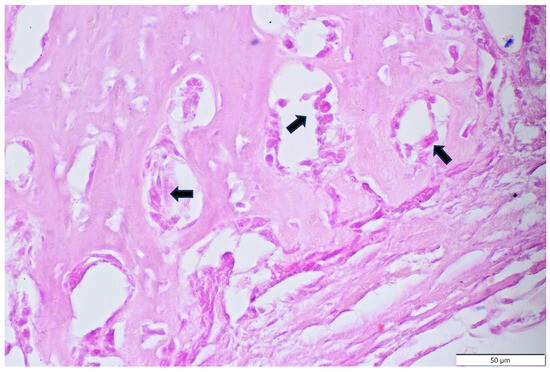

3.3. Results of Microscopic Examination